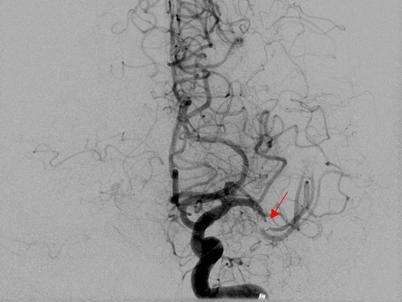

Vigilanzminderung Unruhe Halluzinationen Vollständige neurologische Erholung 37 2019 Peter Borchmann Cologne Lymphoma Group 1. A new study overturns a decades-old theory about the nature of attention and demonstrates that even brief diversions from a task can dramatically improve ones ability to focus on that task for. Cardiology Diagnóstico de una paciente con problemas en las arterias.